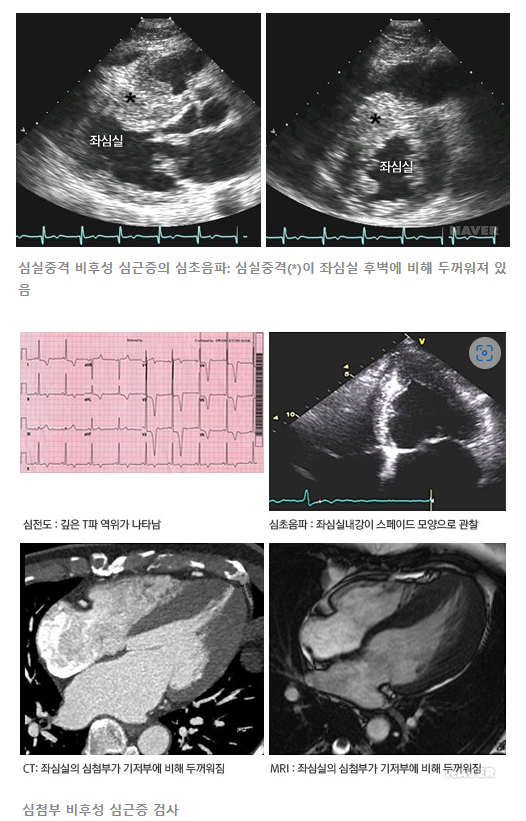

| 비후성 심근병증(Hypertrophic Cardiomyopathy, HCM)이란? 특징, 원인, 증상, 치료 및 수술방법 (1) | 2025.03.04 |